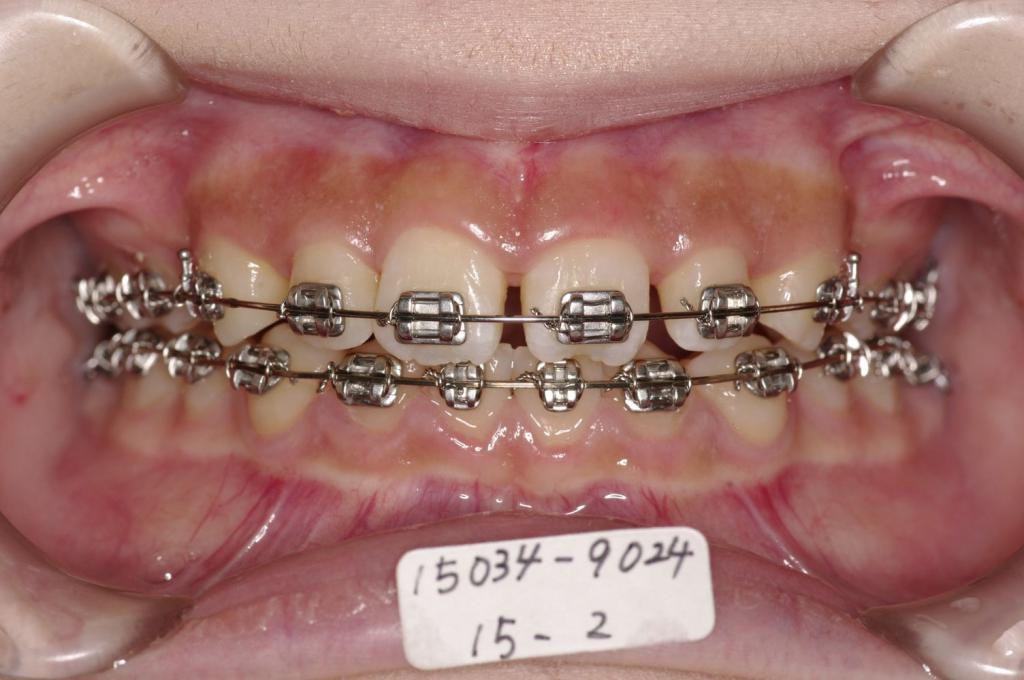

装置の種類及び治療法 診断:両側下顎側切歯先天欠如 過蓋咬合

治療方法および装置:マルチブラケット装置

High pull J-hook headgear

抜歯:右上4 /左上4

右下 /左下

欠損歯:右上 /左上

右下2 /左下2

治療前

歯欠損の矯正治療前口内写真NO.145